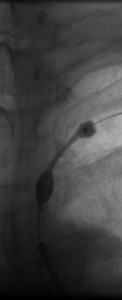

The 4 images you see above were recorded by me during primary stenting of irregular atherosclerotic stenosis of the left subclavian artery in a 54-year-old hispanic female who was referred to my interventional radiology clinic for management of the stenosis. She had presented to her primary care physician with symptoms of hindbrain ischemia upon using her left upper limb and earlier workup confirmed left subclavian arterial stenosis. The 2 top images illustrate the character and severity of her disease, the first image in the bottom row shows the process of balloon-expandable stenting of the disease, while the 2nd image in the bottom row reveals complete elimination of the stenosis and reappearance of the left vertebral and internal mammary arteires, which were invisible on the pre-intervention angiograms reflecting the severity of the stenosis.